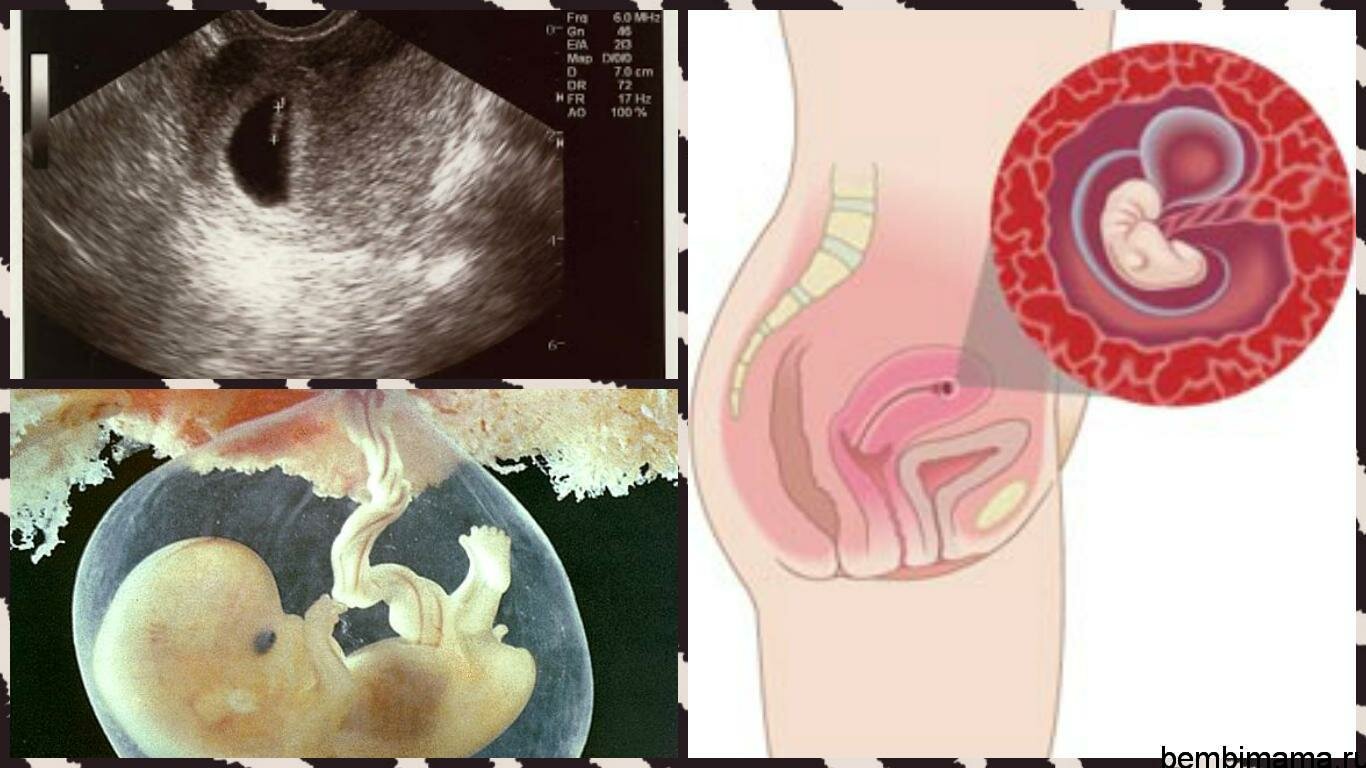

Этапы развития эмбриона человека: 14 недель